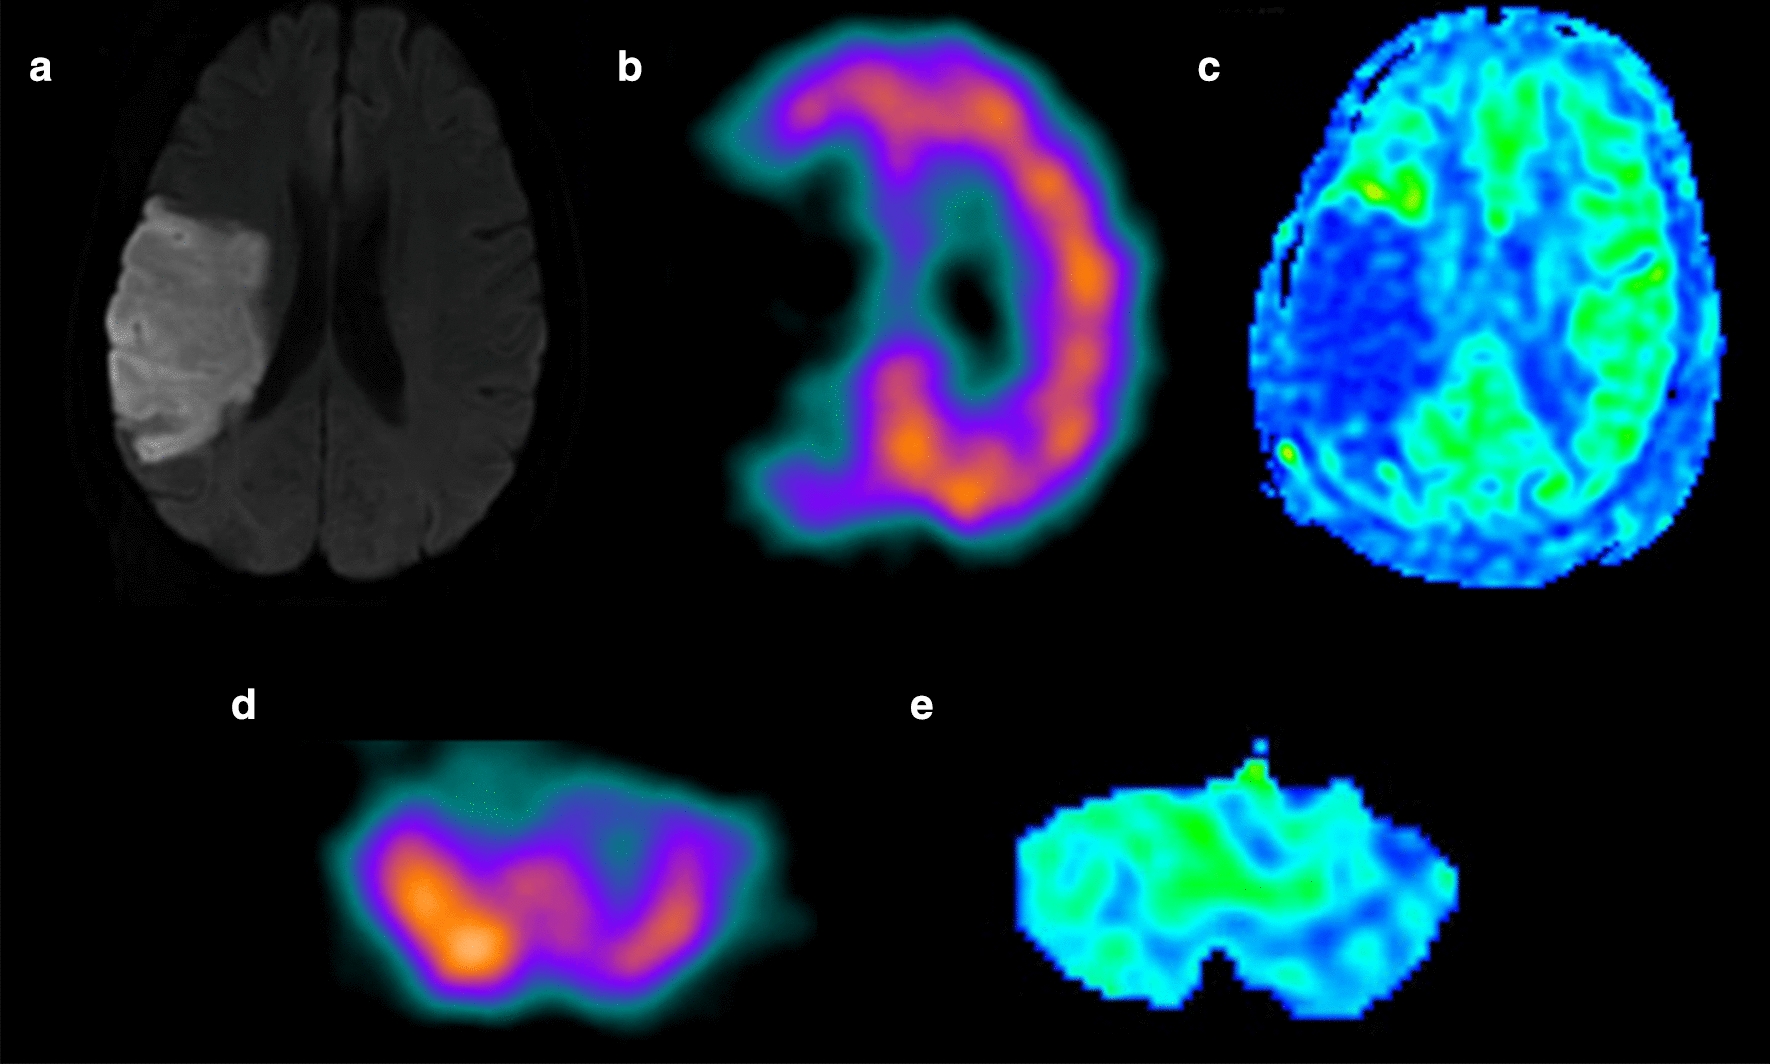

The median CBFASL of ipsilateral cerebellum (39.86 ± 9.43 ml/100 g/min) was significantly increased than that of contralateral cerebellum (33.34 ± 9.87 ml/100 g/min, p < 0.0001) in the CCD-positive group, while no significant difference was detected in the CCD-negative group (p = 0.063). Furthermore the similar phenomenon was also observed in CBFSPECT (Table 2). Figure 1 shows the images of DWI (A), SPECT (B,D) and ASL(C,E) of a representative patients with supratentorial stoke in right parietal for 7 days.

Fig. 1.

A 62‑year‑old man with a history of sudden onset left-sided weakness for 7 days. a Hyperintensity stroke lesion can be recognized in the right temporal lobe on diffusion weighted image. b SPECT and c ASL maps showing hypoperfusion in the same lesion. d SPECT and e ASL images showing hypoperfusion in the contralateral cerebellum hemisphere